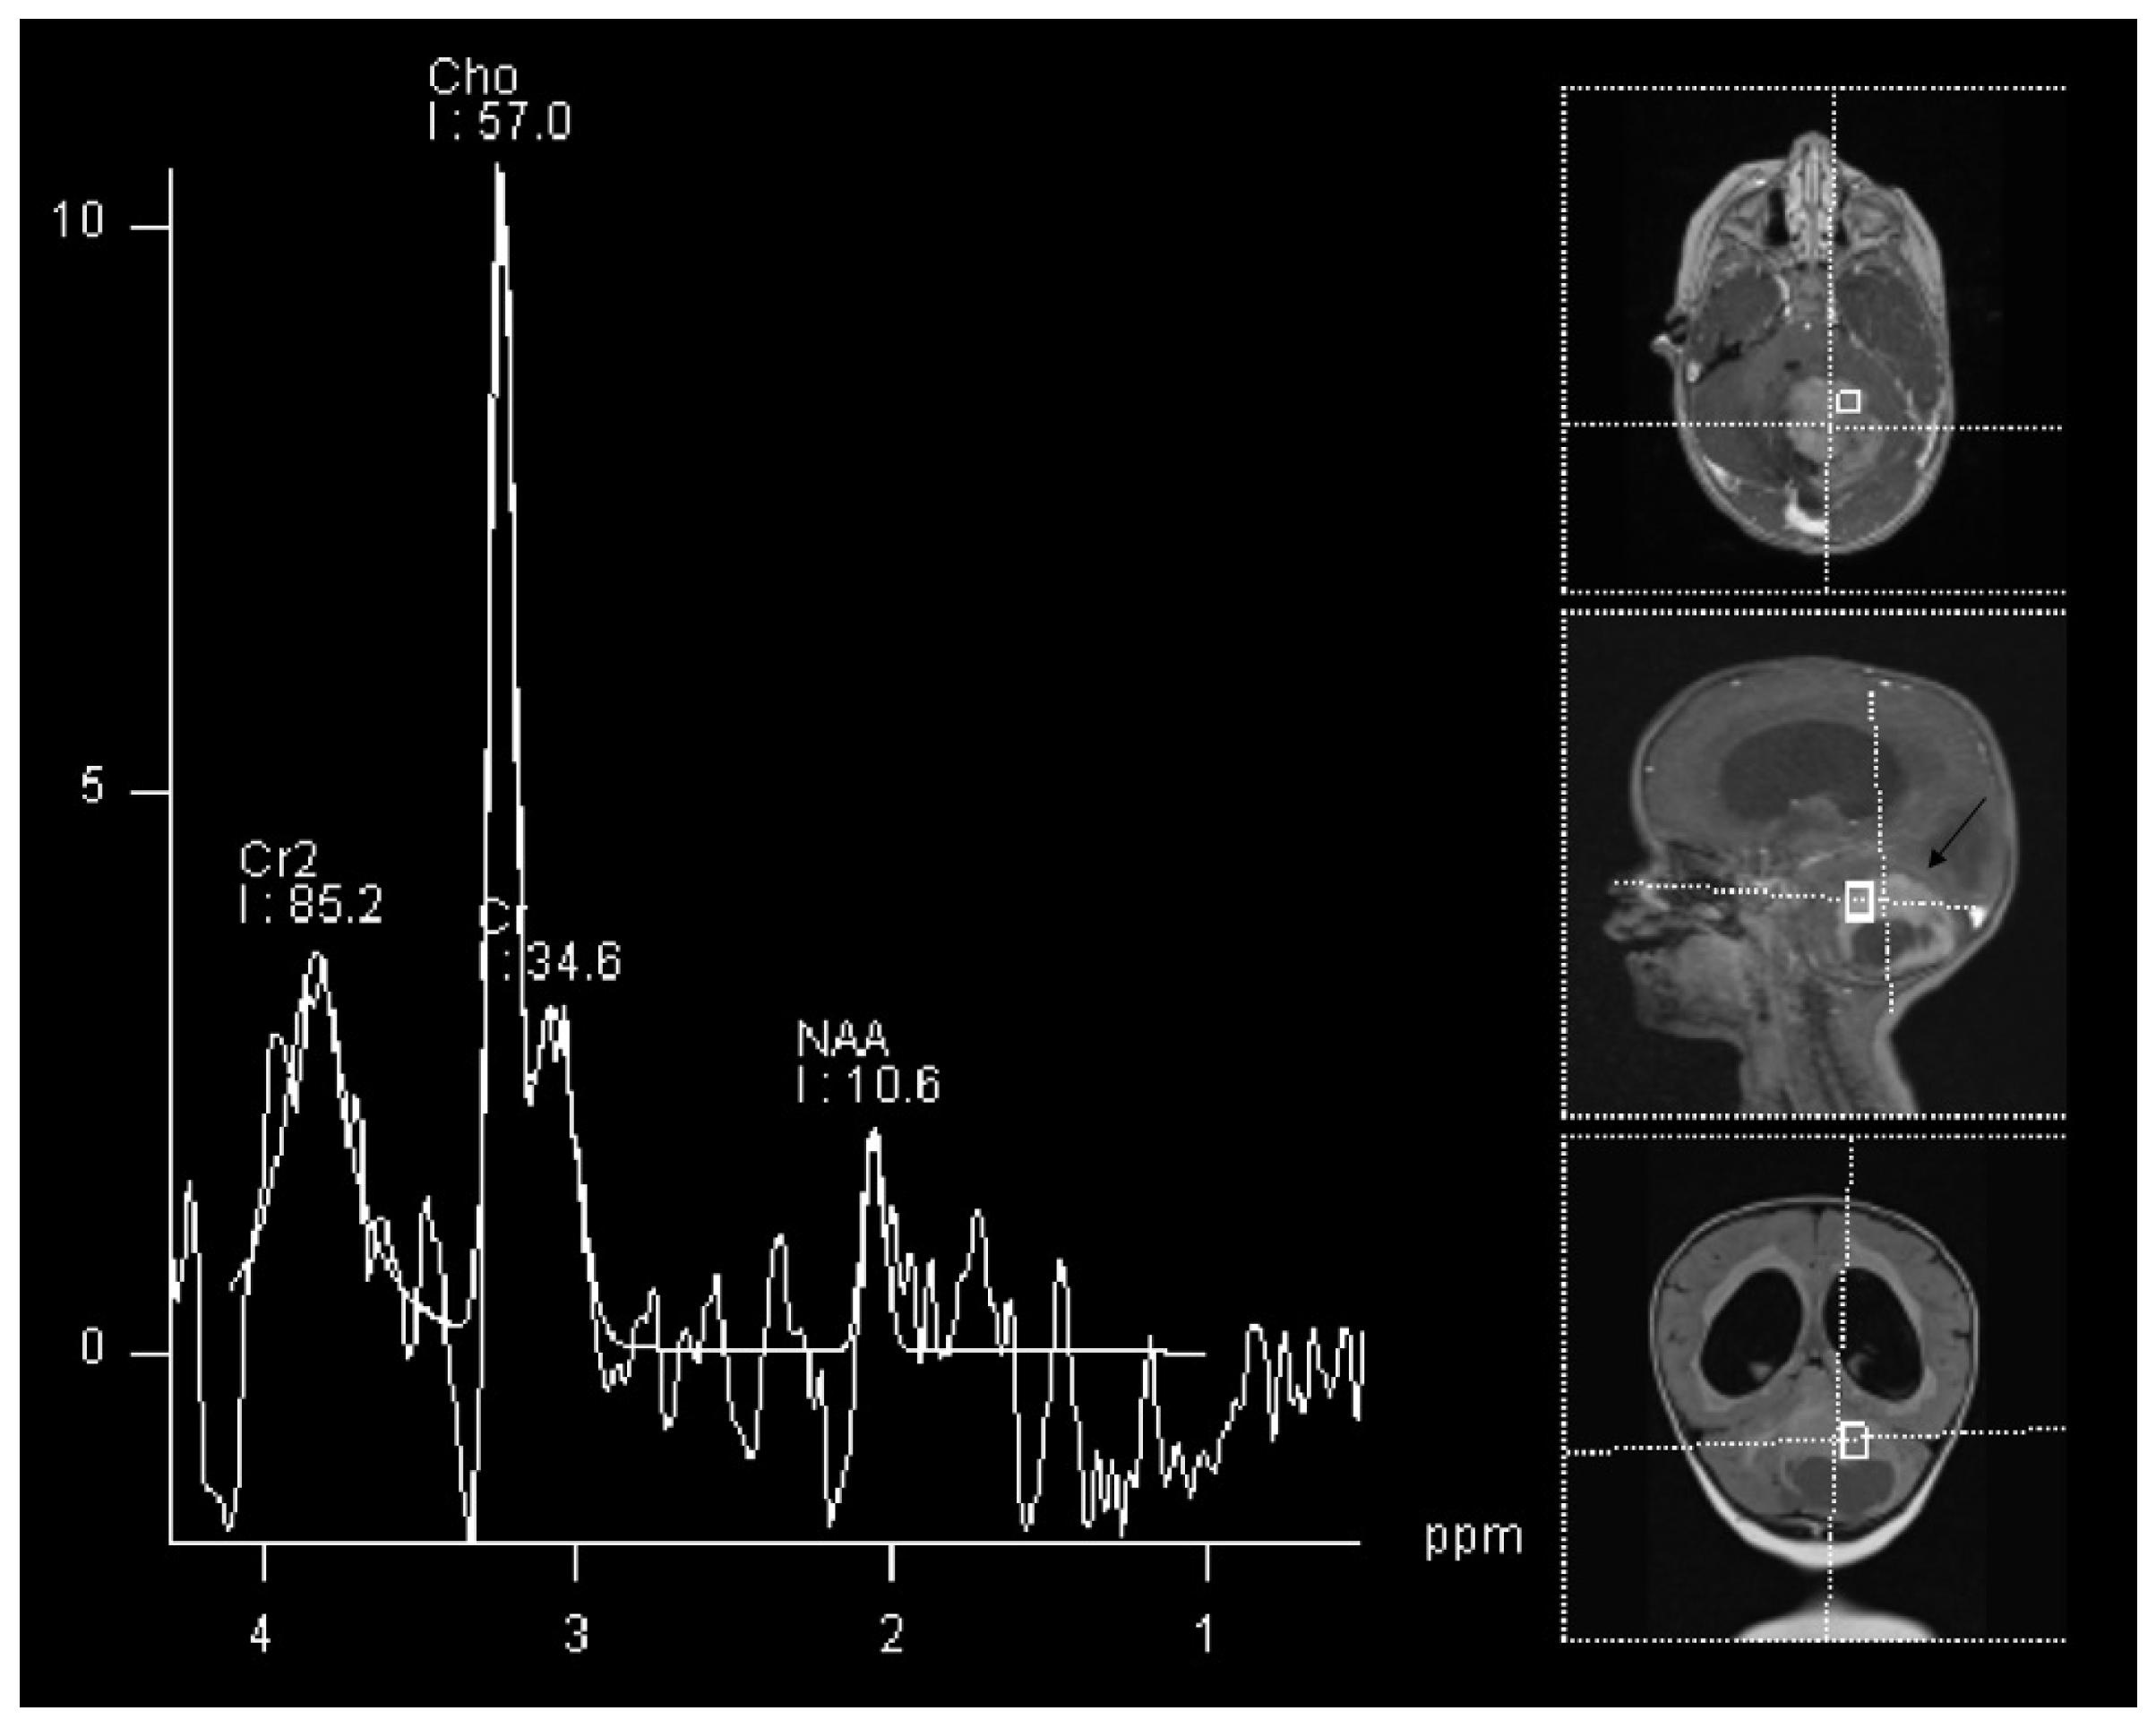

The most common glioma in the pediatric population is pilocytic astrocytoma [35]. This tumor type is not only the most common glioma, but is the most common brain tumor in children in general, accounting for around 15% of all brain tumors in this population [36]. The imaging of the pilocytic astrocytoma is fairly straightforward using regular structural MRI sequences, however, when performed, MRS show a high Cho/NAA and Cho/Cr ratio, and low Cr with a decreased NAA/Cr ratio [37]. These changes can be seen in an example of a 2 year old patient with histologically proven cerebellar pilocitic astrocytoma (Figure 1).

Figure 1. 1H-MRS in a patient (2 Y) with pilocitic astrocytoma (black arrow). Significantly increased Cho and decreased NAA and Cr are observed.